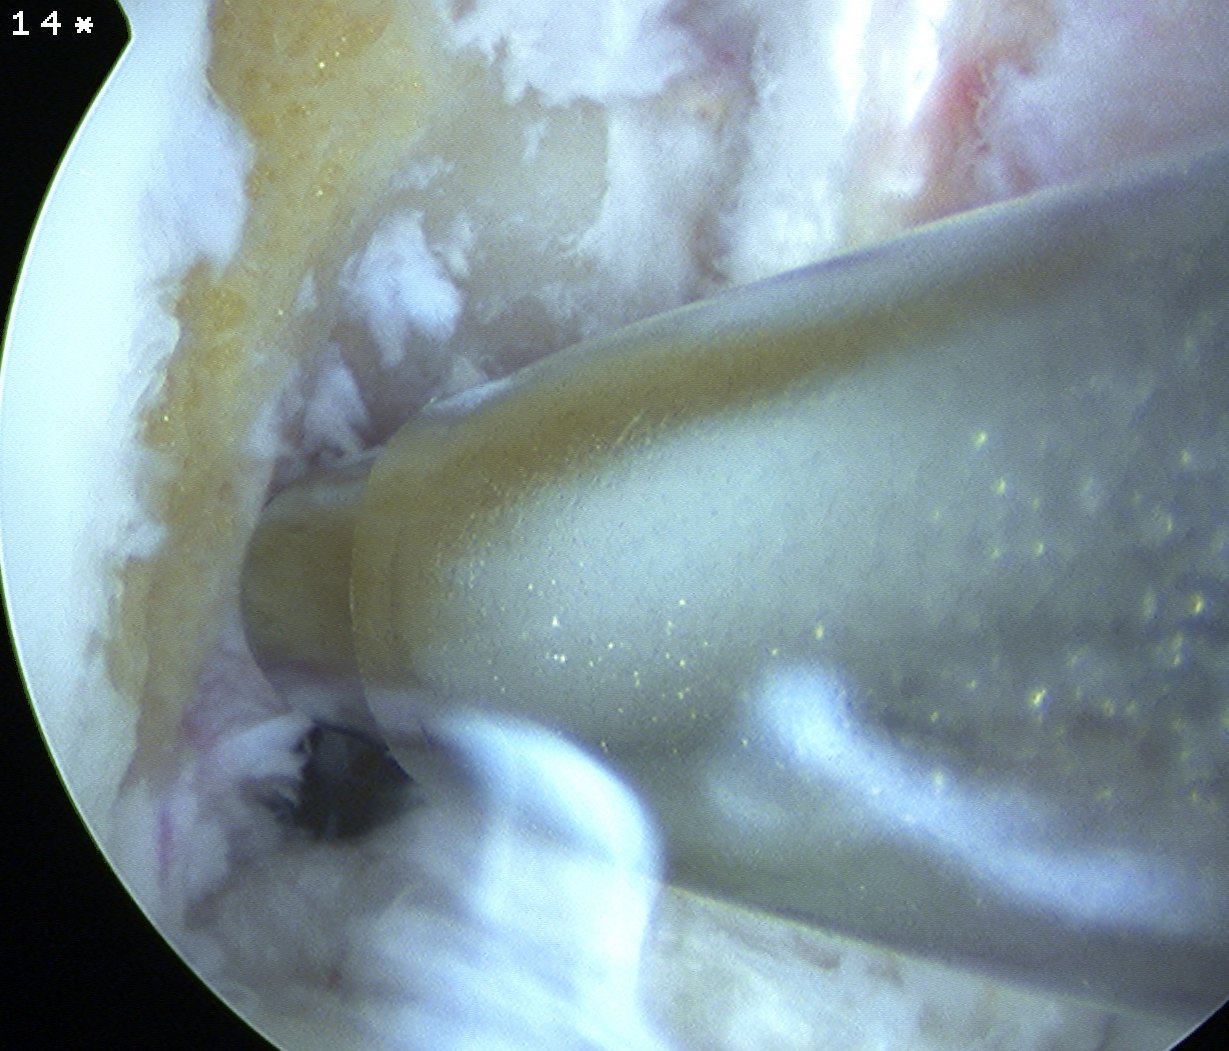

Pass Graft

Retrieve end of 1 nylon loop via tibial tunnel with grasper / probe

- place all 4 sutures of endobutton into loop and pull up through femoral tunnel

- separate sutures

- visualise femoral tunnel with camera

- use the pulling sutures to pull graft up into femoral tunnel

- helpful to wrap about artery forcep for traction

- then use both sutures to ensure that endobutton has flipped (rock each end back and forth)

- tension other end of graft and ensure cannot flip endobutton any further